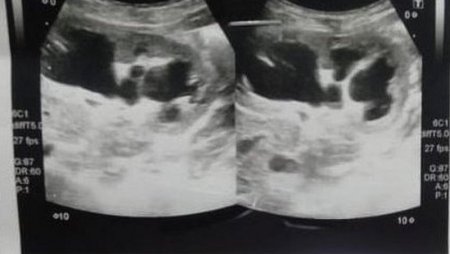

"Коли я оглядав дитину, я відчув якусь пухлину. Я зробив УЗД і [діагностував], що в черевній порожнині є якась кіста. Я навіть не думав, що це може бути щось інше", - каже він.